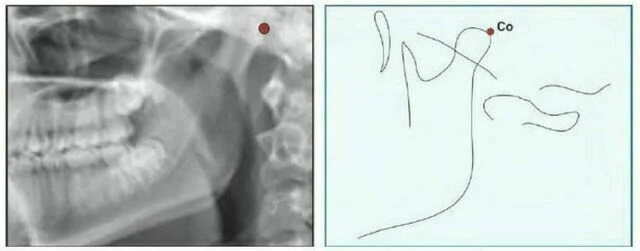

Condylion (Co) là điểm sau nhất và trên nhất ở lồi cầu xương hàm dưới.

Articulare (Ar) Giao điểm của mặt dưới nền sọ và mặt sau của cổ lồi cầu xương hàm dưới. Articulare được sử dụng một cách có hệ thống cùng với Condylion khi điểm này không nhìn thấy rõ. Sự thay đổi của vị trí lồi cầu sẽ làm điểm Artculare dịch chuyển.